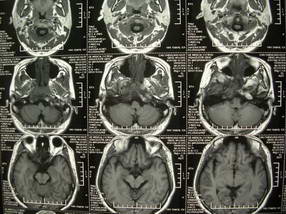

男、30、发现鼻咽部肿瘤侵犯海绵窦,未发现明显淋巴肿。请问国内那家医院治疗鼻咽部肿瘤最好?手术以何种方式为主?病灶可否全部切除?急切期待的大家的帮助。

扫描示鼻咽腔不对称,中度狭窄,右侧咽隐窝消失,局部软组织肿块,鼻咽右侧壁增厚形成肿块,突入鼻咽腔,肿块平扫呈等密度,肿块向深部侵润,右侧翼内外肌受侵,右侧咽旁间隙变窄;向后生长,头长肌界线欠清,向后上生长侵犯同侧颈动脉鞘区。双侧海绵窦增宽,内见软组织影与鼻咽部肿块相连。考虑鼻咽癌。鼻咽癌主要是放射治疗,且效果较好;到当地有治疗设备较大医院治疗即可。